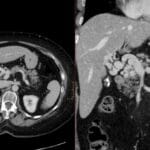

- Radiology Cases: Images with a to-the-point discussion highlighting the specific diagnostic criteria.

Latest Radiology Cases